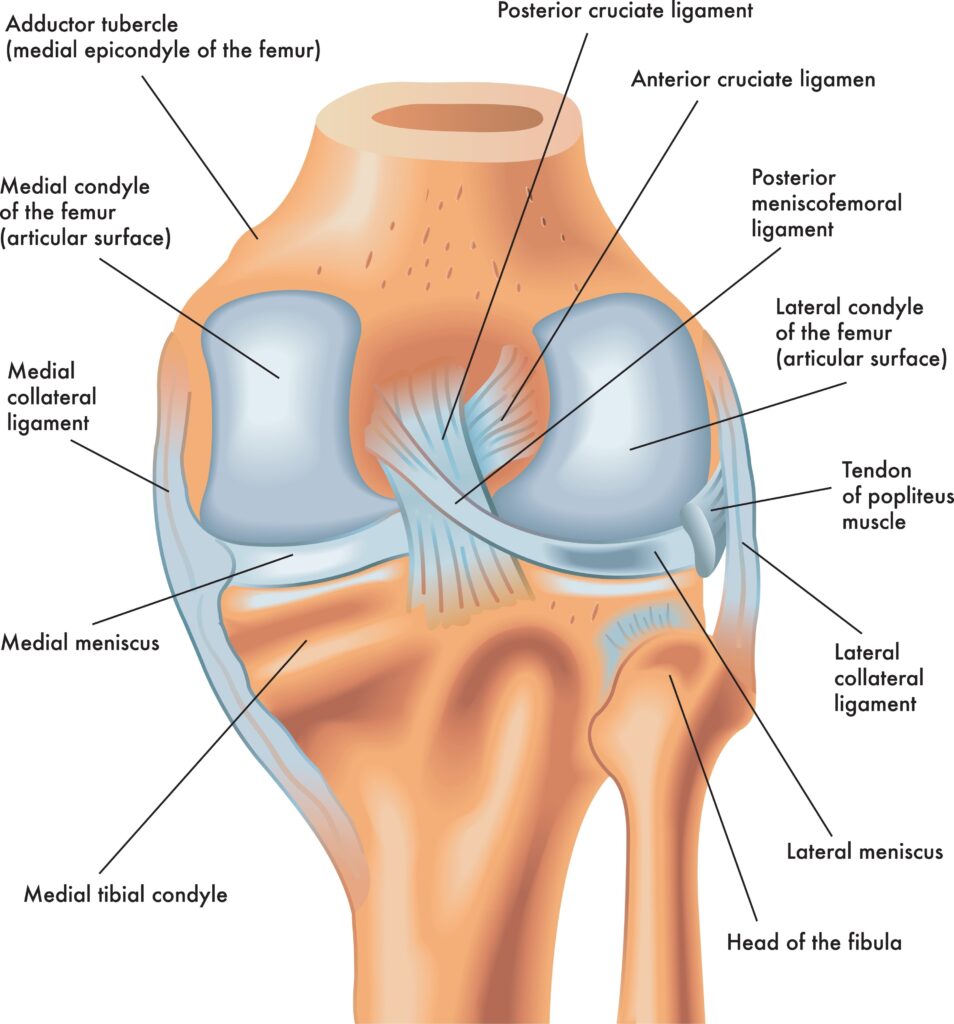

Image-3 Meniscus

3 Meniscus

What is the Meniscus?

The meniscus is a C-shaped cartilage cushion located between the femur and tibia. Each knee has two menisci:

- Medial Meniscus (inner side)

- Lateral Meniscus (outer side)

Function

- Shock absorber for the knee joint

- Helps smooth movement between bones

- Provides stability and distributes body weight evenly